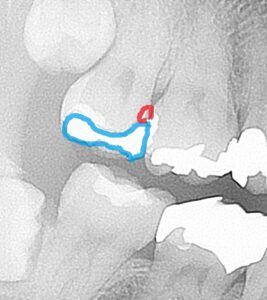

レントゲン写真を見てみると

歯の中の状態が見えてきます。

どこに虫歯があるかというと、

一番奥の歯ですが、

青色の部分が銀歯で、

赤色の場所に虫歯があります。

銀歯の際の部分。歯との接合部から虫歯になってしまっています。

レントゲン写真では黒く隙間みたいになっていますね。